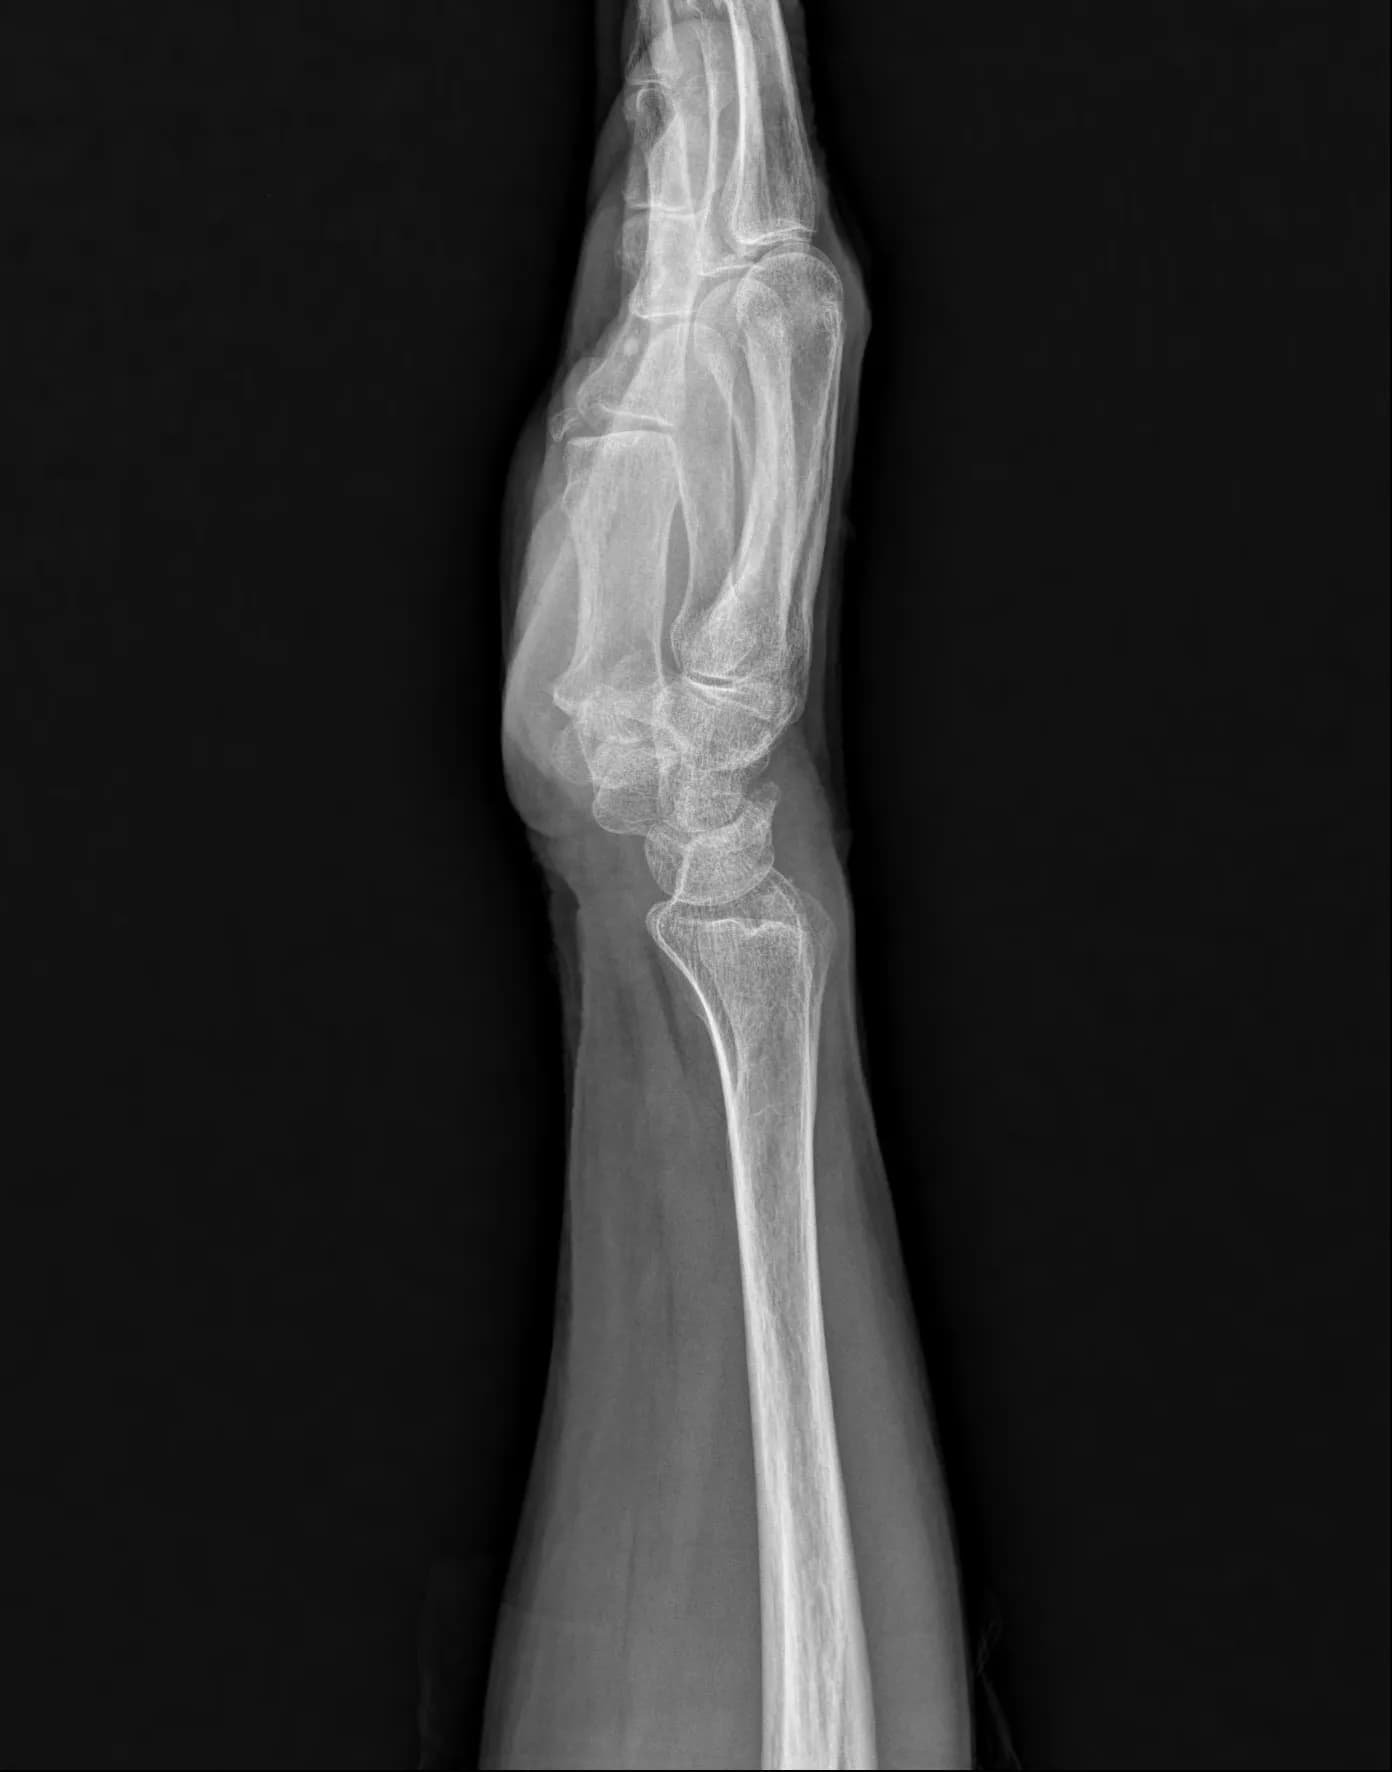

Musculoskeletal X-ray AI Analysis

부위를 클릭하여 결과 이미지를 확인하실 수 있습니다.